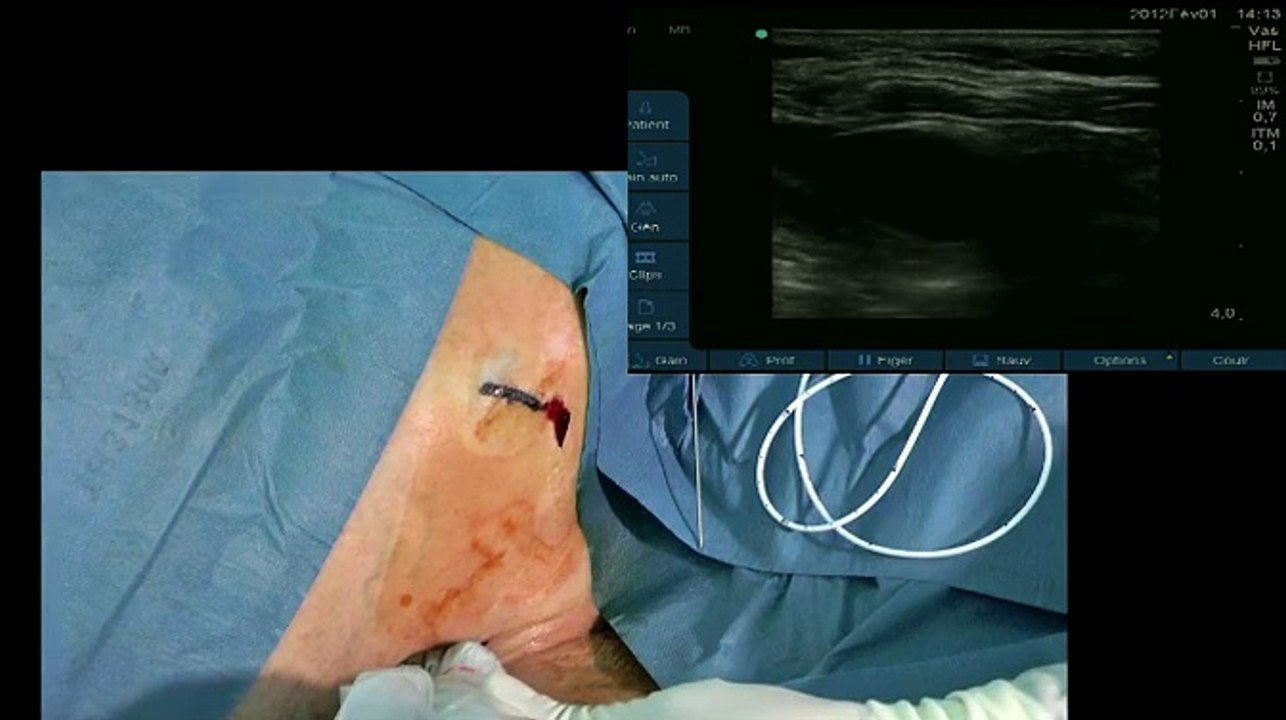

Ultrasound guided venipuncture and J guidewire insertion

Gynécologie

/

Techniques chirurgicales

Case in the box

Presentation of material: port set and Echosite ultrasound system